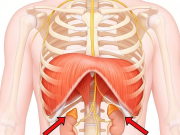

– Fascia quanh tim (pericardial fascia) kết nối với:

– Mạc ngực – cổ – cơ hoành

– Mạc vai – cổ qua cơ pericardial fascia

– Liên quan tới cảm xúc, stress (qua dây phế vị và mạc cơ cổ-trước ngực)

2/ Liên kết cơ – xương – khớp

a/ Xương liên quan:

– Cột sống ngực (T1–T5): Điều khiển thần kinh tim

– Xương ức – sườn: Bảo vệ tim

b/ Cơ liên quan:

– Cơ hoành (Diaphragma): Ảnh hưởng nhịp tim khi thở

– Cơ ức đòn chũm, liên sườn, cơ cổ trước: Căng thẳng có thể ảnh hưởng nhịp tim

(Hình ảnh đính kèm:)